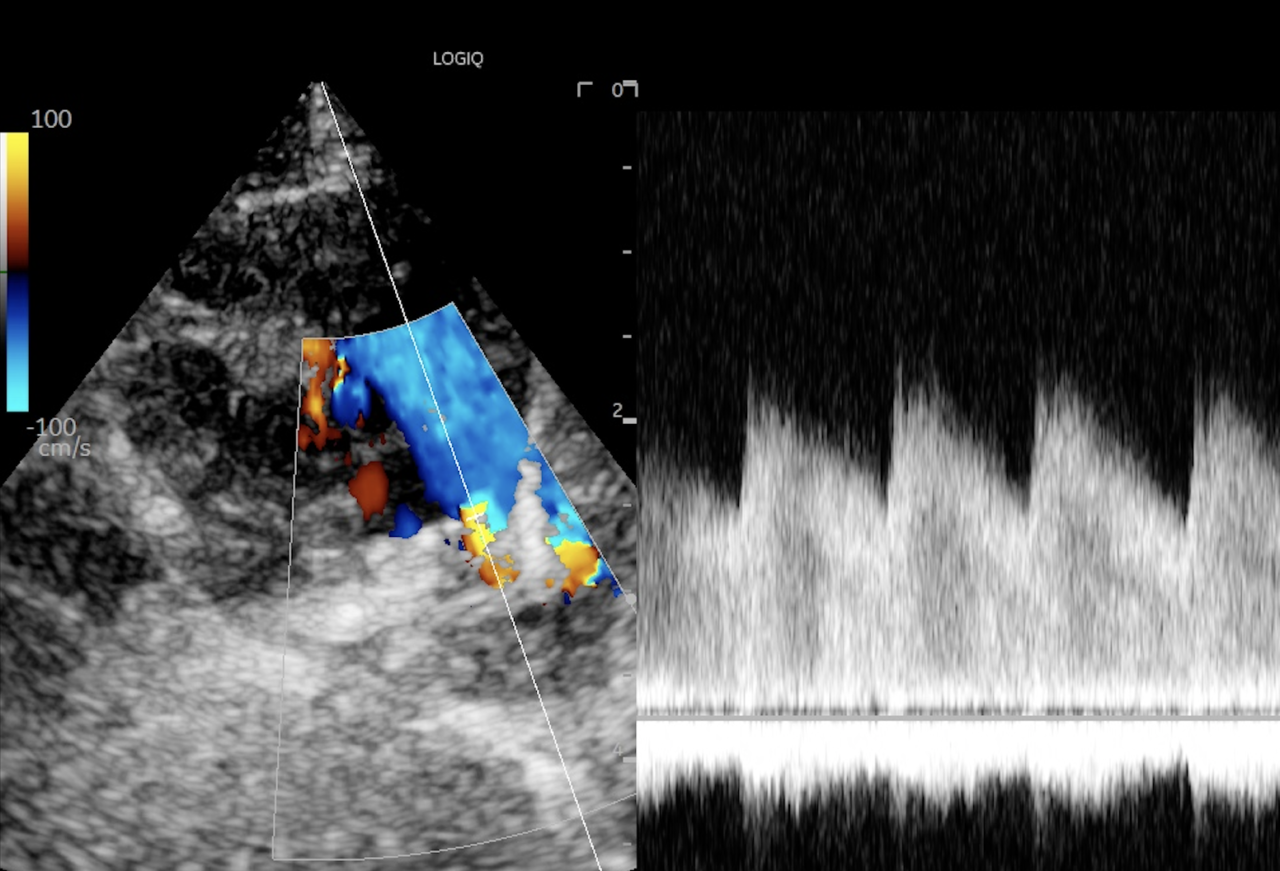

PDAの確定診断は心エコー検査が必要ですが、超音波を当てれば比較的簡単に診断できます。超音波検査で下行大動脈から左肺動脈へと向かう短絡血流を確認することが必要です。

様々なパターンの逆流(モザイクになってる部分が血液の逆流が起こっている)

逆流している血液の波形

病気が確定出来たら検査時点での病状の状態を把握する必要があるため、レントゲンや心電図、血液検査などを含めた心機能検査をして手術の予定を決めます。心機能検査のための超音波はとても重要でこれは血液の流速や、動脈管の太さなどなるべく正確に知りたいので多少の技術が必要です。その血流波形を確認して最大血流速度が3.5m/sec以下の場合は、肺高血圧症の合併症も疑わなければならないため、検査による描出と計測はとても重要です。